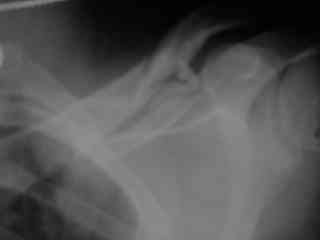

C> Postupil ko mne bolnoi s perelomom obeih kluchits, neznachitelny

C> pneumotorakx sleva.

Накостный остосинтез обех ключиц в одну сессию рекон.пластиной в условиях интубационного наркоза с положительным ПДКВ (+ 5-7 мм вод. ст.) и интраоперационным контролем степени пневмоторакса. Возможно, дренирование плевральной полости слева, по результату рентгенконтроля, по Бюлау.

Справа перелом практически поперечный, можно попробовать интрамедуллярно стержнем. Личного опыта правда не имею, у нас стандартом при оперативном лечении переломов ключицы является тот же остеосинтез пластиной. Но в литературе описана методика даже закрытого остеосинтеза - так, в порядке обсуждения.